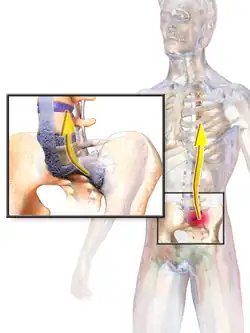

Ankylosing spondylitis (AS) is a type of arthritis from the disease spectrum of axial spondyloarthritis.[5] It is characterized by long-term inflammation of the joints of the spine, typically where the spine joins the pelvis.[2] With AS, eye and bowel problems—as well as back pain—may occur.[2] Joint mobility in the affected areas sometimes worsens over time.[2][6] Ankylosing spondylitis is believed to involve a combination of genetic and environmental factors.[2] More than 90% of people affected in the UK have a specific human leukocyte antigen known as the HLA-B27 antigen.[7] The underlying mechanism is believed to be autoimmune or autoinflammatory.[8] Diagnosis is based on symptoms with support from medical imaging and blood tests.[2] AS is a type of seronegative spondyloarthropathy, meaning that tests show no presence of rheumatoid factor (RF) antibodies.[2]

AS can occur in any part of the spine or the entire spine, often with pain localized to either buttock or the back of the thigh from the sacroiliac joint. Arthritis in the hips and shoulders may also occur. When the condition presents before the age of 18, AS is more likely to cause pain and swelling of large lower limb joints, such as the knees.[13] In prepubescent cases, pain and swelling may also manifest in the ankles and feet where heel pain and enthesopathy commonly develop.[13] Less common occurrences include ectasia of the sacral nerve root sheaths.[14]